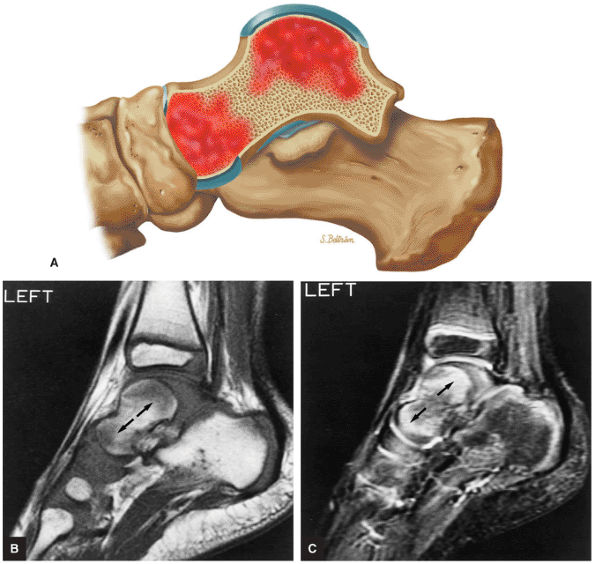

FIGURE 5.92 ● Anterolateral and posteromedial locations of osteochondral lesions of the talus. The lateral lesions tend to be shallower and wafer-shaped, whereas the medial lesions are deeper and cup-shaped.

FIGURE 5.93 ● Medial cup-shaped osteochondral lesion (OLT). Medial OLTs are more common than lateral ones, but lateral lesions are associated with trauma in over 90% of cases. Medial lesions are ascribed to trauma in about 70% of cases. Coronal FS PD FSE image.